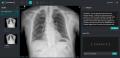

インタビューに先立ち、DEEPNOIDのソリューション全体について説明を求めた。キム専務は「M4CXRは胸部X線データを基に読影所見書のドラフトを自動生成するソリューションだ。技術面では2015年からディープラーニング研究を進め、MRA(磁気共鳴血管造影)を用いた脳動脈瘤検出や、各種病理画像を通じた大腸がん、腎がん、胃がん分析・検出技術などを開発してきた」と説明した。

DEEPNOIDの胸部X線データ分析および読影所見書生成AI「M4CXR」。所見書生成にFuriosaAIのNPUが導入される予定だ / 出典=DEEPNOID

これを基に、AIベースの胸部X線診断支援ソリューション「DEEP:CHEST(ディープ:チェスト)」を開発し、現在はM4CXRへと機能を高度化している。加えて、脳MRA向けのDEEP:NEURO(ディープ:ニューロ)、肺疾患対応のDEEP:LUNG(ディープ:ラング)など医療AIサービスも展開している。中でもDEEP:NEUROは革新医療機器に指定され、非保険診療でも診療報酬が認められている点が特徴だ。産業用X線向けのSkymaru:Security(スカイマル:セキュリティ)、DEEP:Security(ディープ:セキュリティ)、DEEP:Factory(ディープ:ファクトリー)といったソリューションも手掛けている。